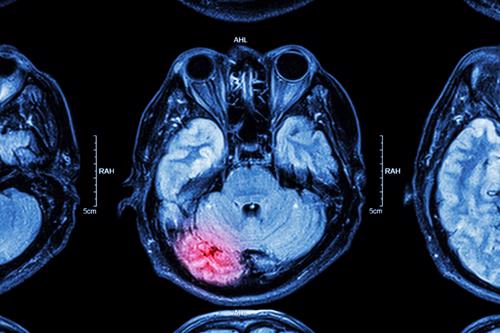

Hypoxia

The brain needs a continuous supply of oxygen to function properly.

If that supply is interrupted, it can cause a hypoxic brain injury.

A hypoxic brain injury occurs if the level of oxygen that’s being supplied to the brain is not sufficient enough to maintain normal brain function.

Medical complications such as strokes, infections, and tumors can cause traumatic brain injuries too.